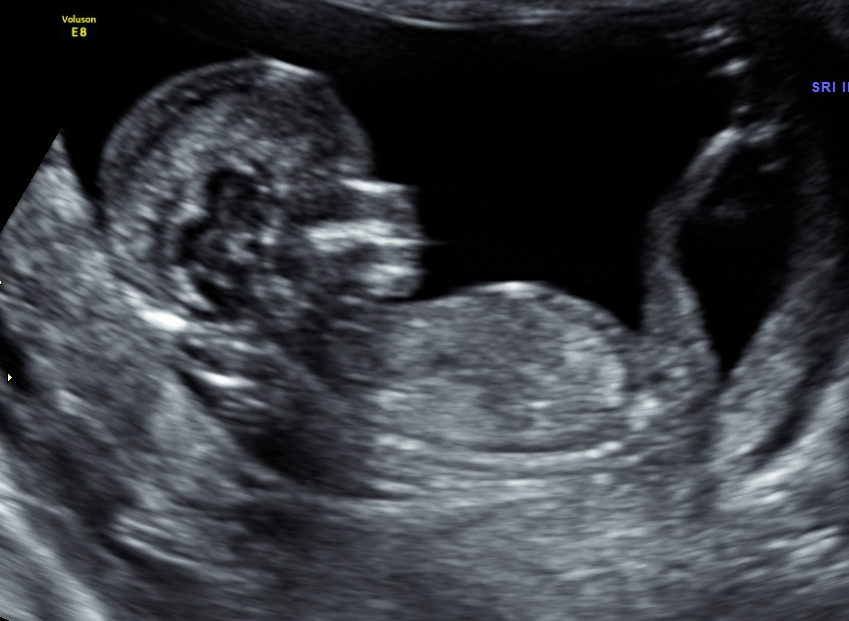

Hi, I had my NT scan last week. First pic you can see the skull. 2nd pic: Is there a nub behind the legs? Any suggestions please?

So you think it could be both when you look at the skull? I thinkt the first pic looks more like a girl, 2nd more boy. I donīt know.